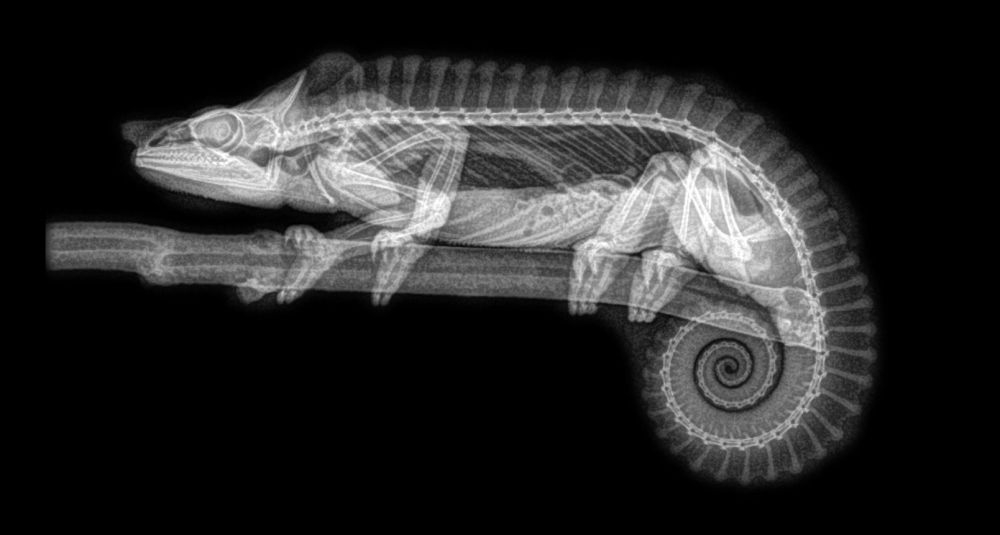

ABD'nin Oregon eyaletinde bulunan bir hayvanat bahçesi, hayvanların rutin sağlık kontrolleri sırasında çekilen X-Ray görüntülerini paylaştı.

Sağlık kontrolleri sırasında bazı hayvanlara röntgen çektiklerini söyleyen hayvanat bahçesi yetkilileri, bu yöntem sayesinde sağlık değerlendirmelerinin daha kolay yapıldığını ifade etti.